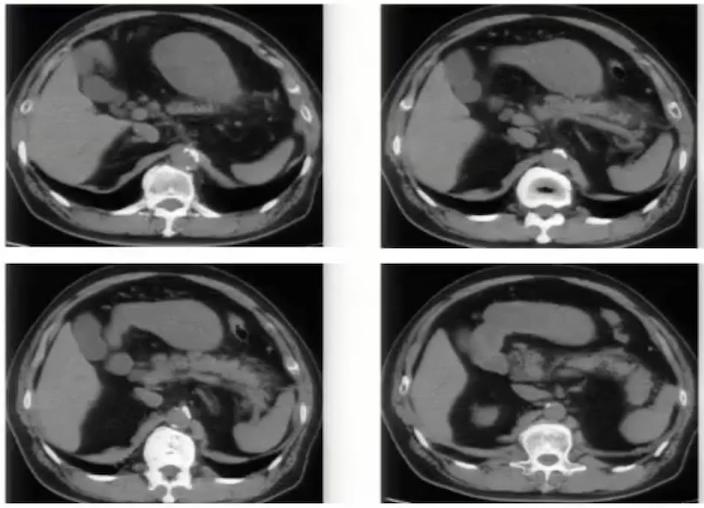

图10:中腹部增强CT显示腹主动脉前后各走行一左肾静脉,分别汇入下腔静脉

图11:腹主动脉两侧均有下腔静脉影,左侧下腔静脉向上与左肾静脉汇合后,在腹主动脉前方绕行,移行为右侧下腔静脉